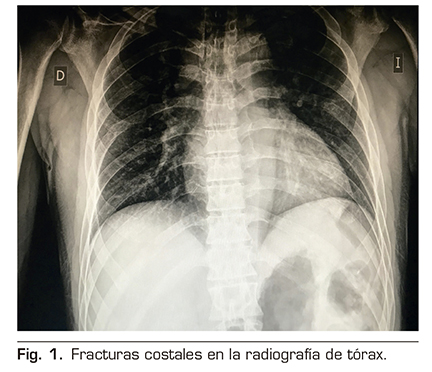

Figura 1